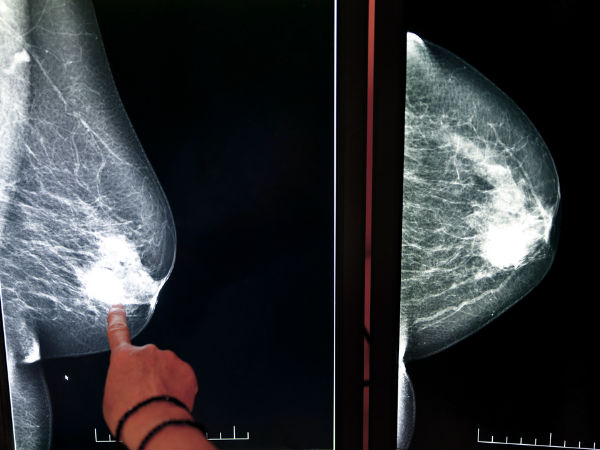

कई महिलाओं ने बताया कि उन्हें ऐसा महसूस होता है जैसे उनके स्तनों में कोई गाँठ हो। वैसे तो स्तनों में किसी भी तरह की गांठ होना ब्रेस्ट कैंसर का मुख्य लक्षण है लेकिन इस मामले में यह कैंसर का लक्षण नहीं बल्कि किसी और कारण से है।

स्तनों में दर्द होने के अन्य कारण : स्तनों में दर्द होना हमेशा ब्रेस्ट कैंसर का ही लक्षण नहीं होता है बल्कि अधिकतर बार मेनोपॉज या प्रेगनेंसी पीरियड में भी ये दर्द करने लगता है। प्रेगनेंसी में यह दर्द काफी बढ़ जाता है और कई बार दर्द के साथ साथ मिचली या उलटी आने जैसी समस्याएँ भी होने लगती है। ऐसा कुछ भी महसूस होने पर तुरंत डॉक्टर से अपनी जांच करवाएं।